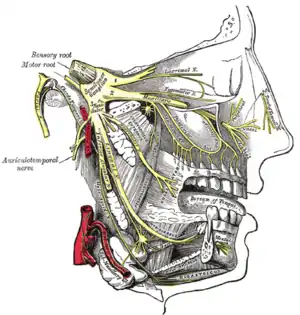

Plan of branches of internal maxillary artery. Distribution of the maxillary and mandibular nerves, and the submaxillary ganglion.

Distribution of the maxillary and mandibular nerves, and the submaxillary ganglion.